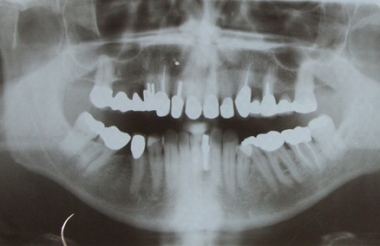

Die Radiologie liefert zweidimensionale Röntgenbilder mit Informationen zu dem allgemeinen Zustand der Zähne und des Knochens. Die Analyse der Knochensubstanz erfolgt über strahlungsarmes, digitales Röntgen. Die Bilder des Orthopantogramms (OPG) stehen als digitale Daten zur Verfügung. Panoramabilder lassen sich auf dem Computerbildschirm analysieren. Digitales Röntgen verzichtet auf die klassischen Filme. Die Daten/Bilder werden direkt an einen Computer geleitet. Die digitale Form dieser Aufnahme ist wesentlich besser lesbar und genauer als klassische Röntgenaufnahmen.

Für eine sichere Implantatplanung in schwierigeren Situationen reichen diese zweidimensionalen Panoramaschichtaufnahmen nicht aus, da die Beurteilung des Knochens begrenzt ist. Es fehlt die räumliche Vorstellung des Knochens. Das Implantatlager kann nicht vertikal abgebildet werden. Dies birgt die Gefahr einer Verletzung anatomischer Strukturen.